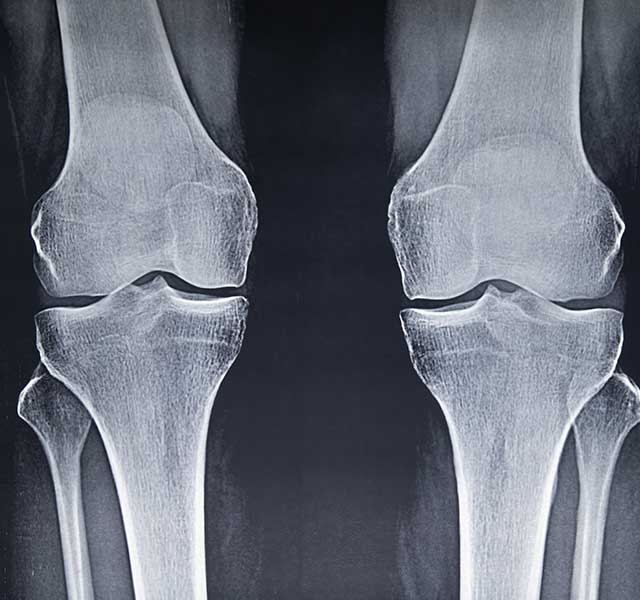

Osteoarthritis – a degenerative joint disease – can be challenging to live with. It causes pain and stiffness, making it difficult to go about your daily life. Virtually no one is immune to it as they get older, since it’s caused by cartilage wearing down over the years, says Ramsey Shehab, M.D., a sports medicine physician at Henry Ford Health.

“Age is the greatest risk factor for osteoarthritis, but genetics and getting injured at a young age can also play into when someone will develop osteoarthritis – and how severe it will be,” says Dr. Shehab.

The only cure right now for osteoarthritis is joint replacement surgery, which is usually an option after you’ve cycled through the above, lesser invasive options to manage symptoms.

“While some people are wary of joint replacement surgery, we have great technology that makes joint replacements longer lasting and feel more like natural joints,” says Dr. Shehab. “It can really be life changing.”